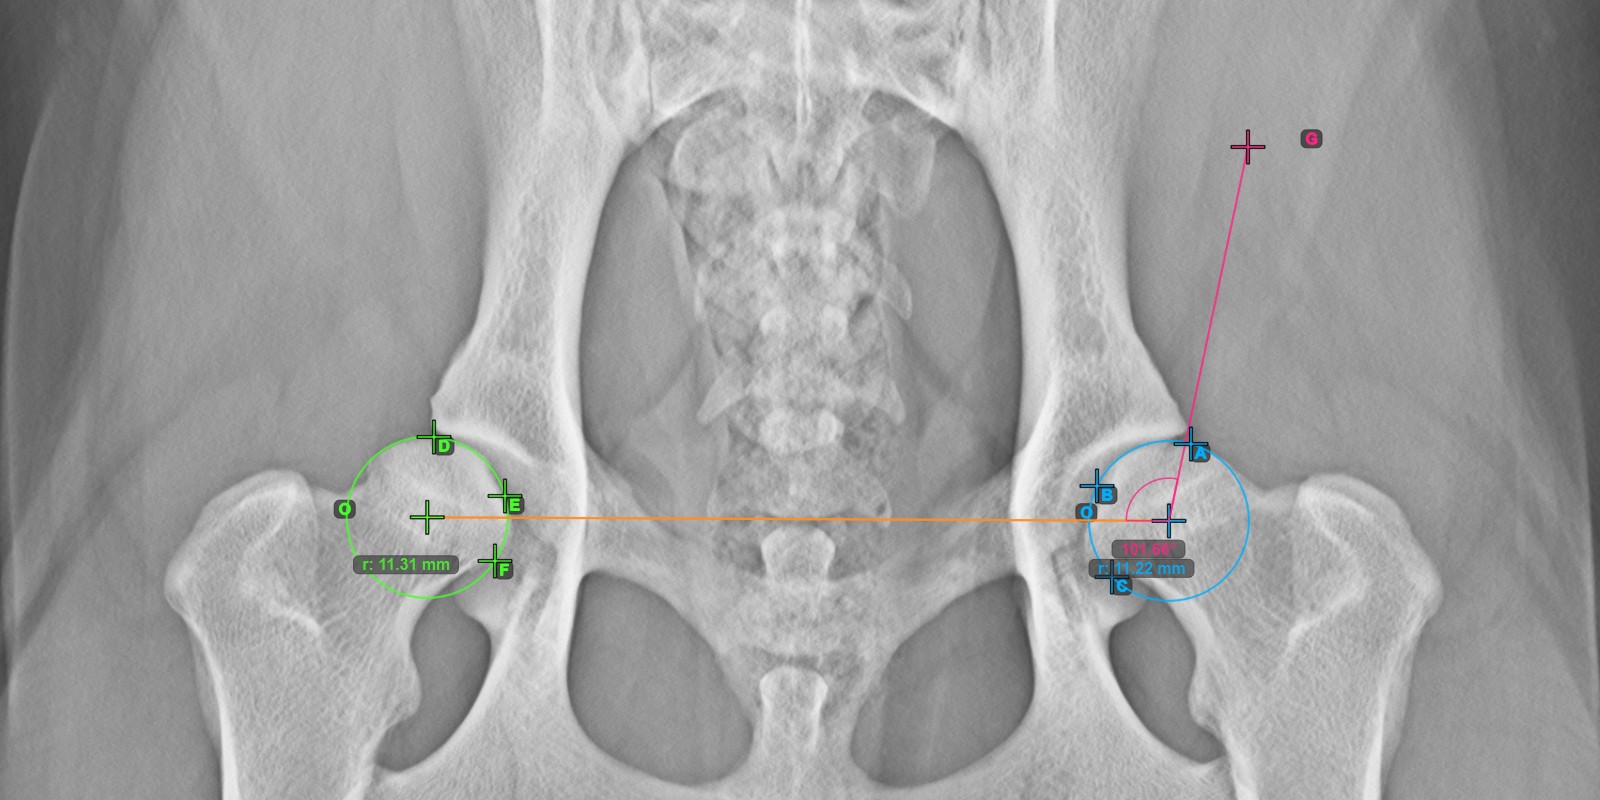

Start the measurement by marking the three points on the articular surface of the left Caput Femoris.

Mark the three points on the articular surface of the left Caput Femoris (outside of the Fovea Capitilis). Regardless of the order, make sure to mark the most cranial point, the most caudal point and the midpoint of the femoral head. A circle will be automatically constructed based on the three placed points.

The image below depicts the typical placement of the three points on the articular surface of the left Caput Femoris.